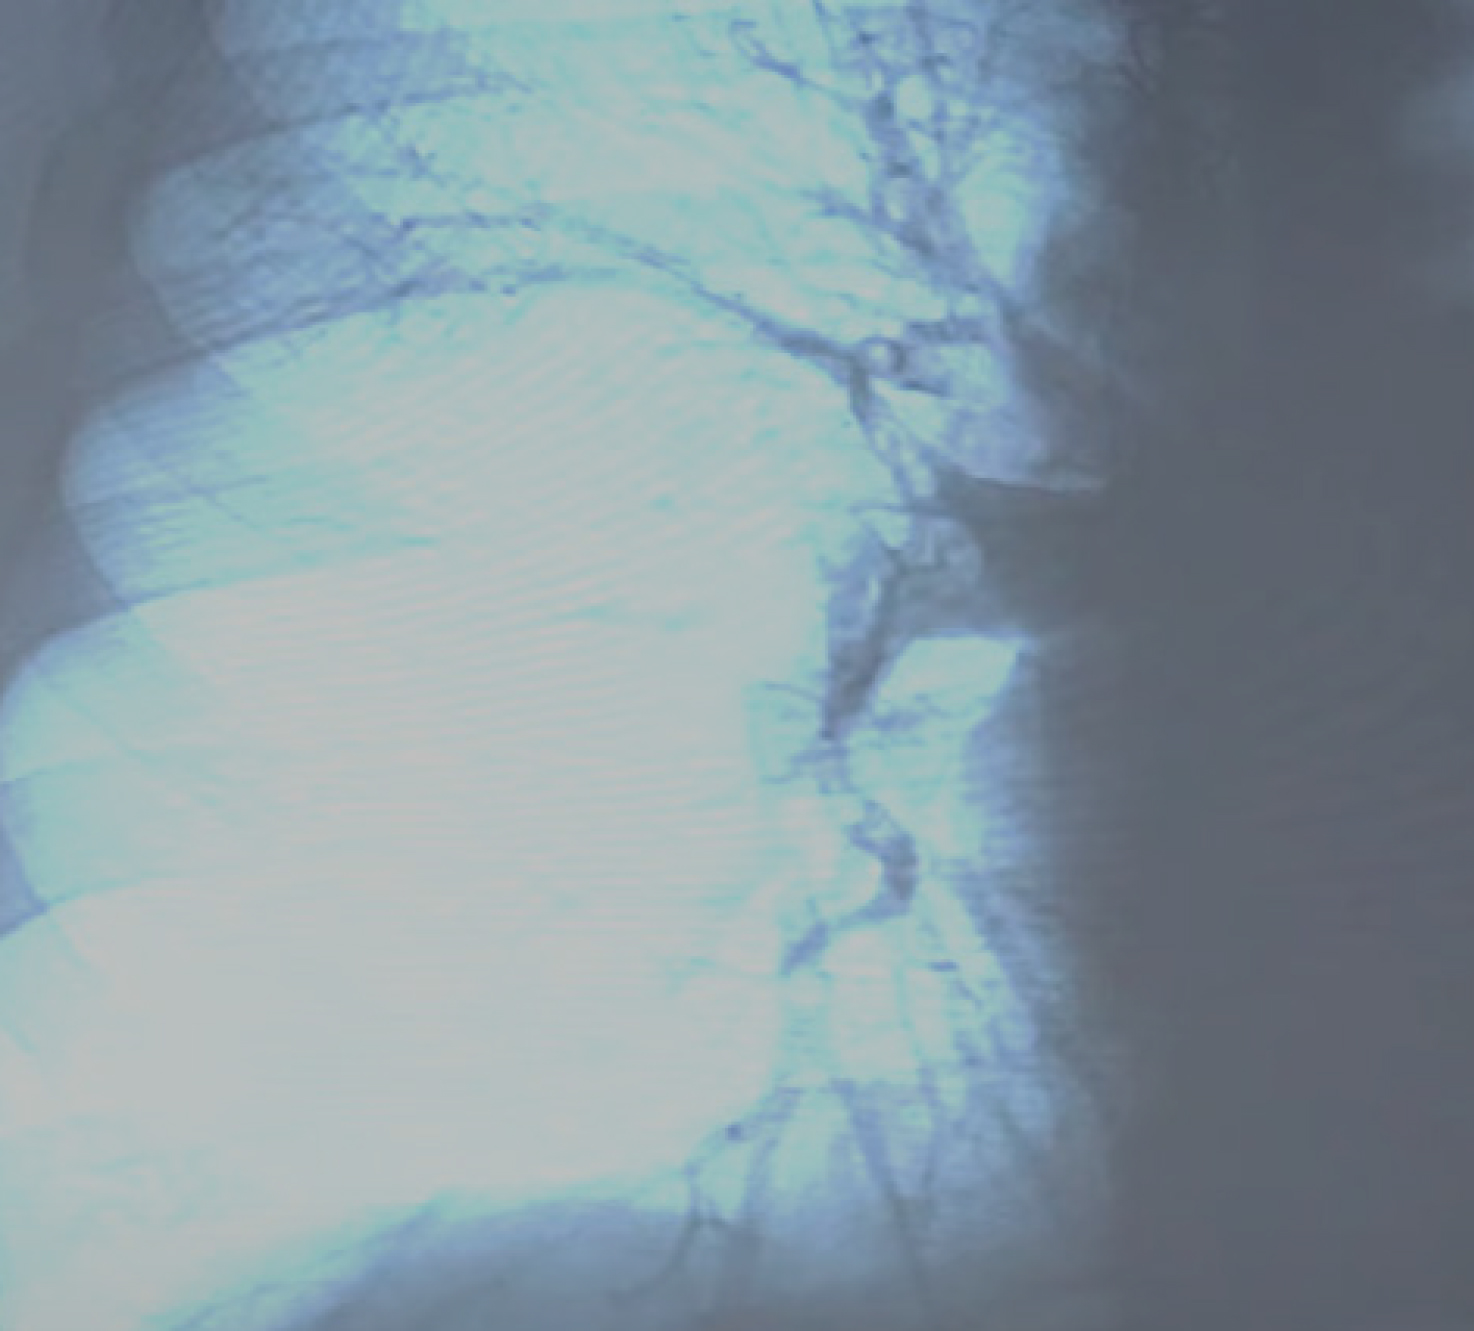

При осмотре нижних конечностей выявлены варикозные изменения поверхностных вен. Пациентке проведено ультразвуковое исследование вен нижних конечностей. В глубокой вене бедра выявлен флотирующий тромб (рис. 1 а), поверхностные вены расширены (рис. 1 б), кровоток в коммуникантах инверсирован.

Рис. 1. Данные УЗИ вен нижних конечностей. Флотирующий тромб в системе глубокой бедренной вены: а – варикозно расширенные поверхностные вены нижней конечности; б – источник ТЭЛА, глубокая венозная система ноги (пристеночная часть тромба, оставшаяся после случившейся эмболии)